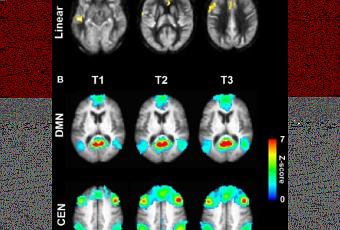

Pouvoir renforcer la capacité intellectuelle n’est pas une illusion : Des changements physiques dûment constatés dans le cerveau (voir évolution de différentes caractéristiques aux différentes étapes de la formation sur visuel ci-contre) et des scores démontrant l’amélioration cognitive en réponse à un entraînement mental basé sur la stratégie, démontrent le potentiel de neuro-régénération du cerveau.